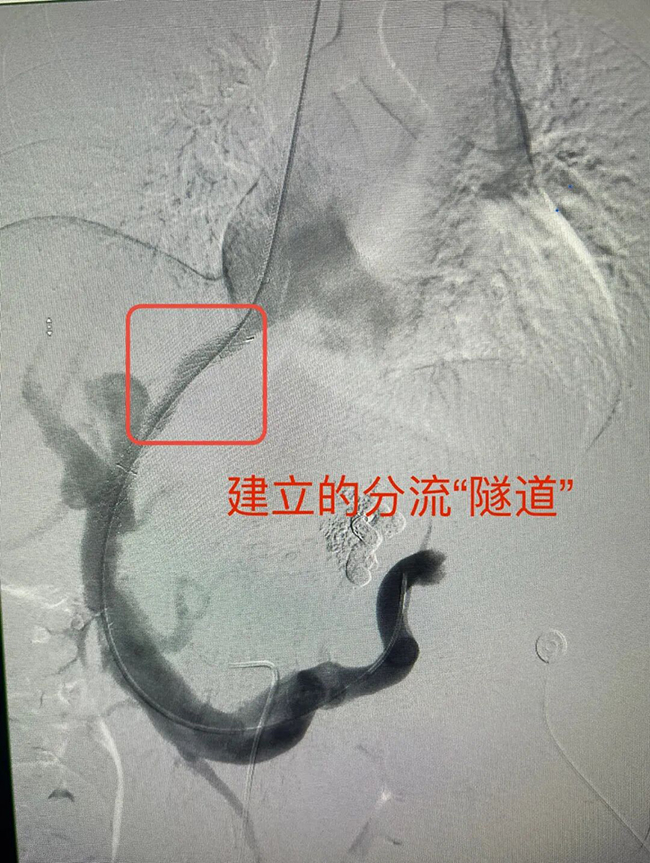

传统的内科药物治疗或局部止血,门静脉高压的问题无法解决,再出血风险高。而TIPS手术,正是直击“源头”的治本之策。赵辉教授用了一个生动的比喻:“这就像在人体内部实施了都江堰工程,疏堵结合。在肝静脉和高压的门静脉之间,用微创技术建立一条人工分流‘隧道’,将淤滞高压门静脉的血液分流一部分到肝静脉,降低门静脉压力,从而从根源上降低静脉曲张再破裂风险。同时,我们还能精准栓塞出血的曲张静脉,达到‘既堵又疏’的双重效果。”

手术团队为孙女士进行了详尽的术前评估。手术当日,赵辉教授凭借丰富经验,精准穿刺、成功建立分流道、彻底栓塞出血血管。整个微创手术历时约1.5小时,过程顺利,术后第3天,她便康复出院。